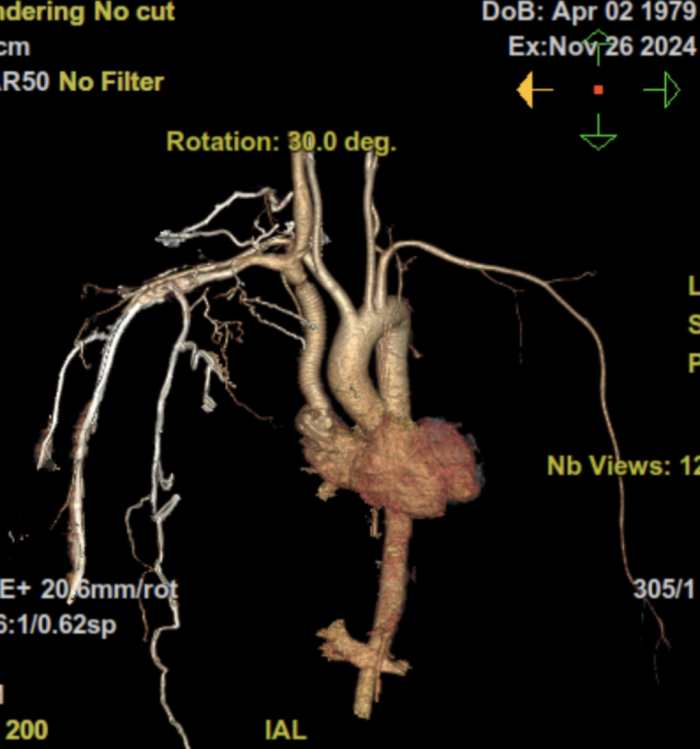

患者术前CT结果提示纵隔肿瘤侵犯上腔静脉及其所有属支

第二天,临桂院区高端256排增强CT检查结果证实了梁恒星主任的诊断——颜女士的纵隔肿瘤很可能是恶性胸腺瘤,并且病变已经外侵,完全阻断了颜女士的上腔静脉,导致上半身、尤其是颅内血液回流受阻,如果不及时手术,可能会出现严重的脑水肿并威胁生命。而恶性胸腺瘤保守治疗效果不确切,不能保证患者能在短时间内解除上半身血流梗阻,一旦决策错误,将带来灾难性后果。